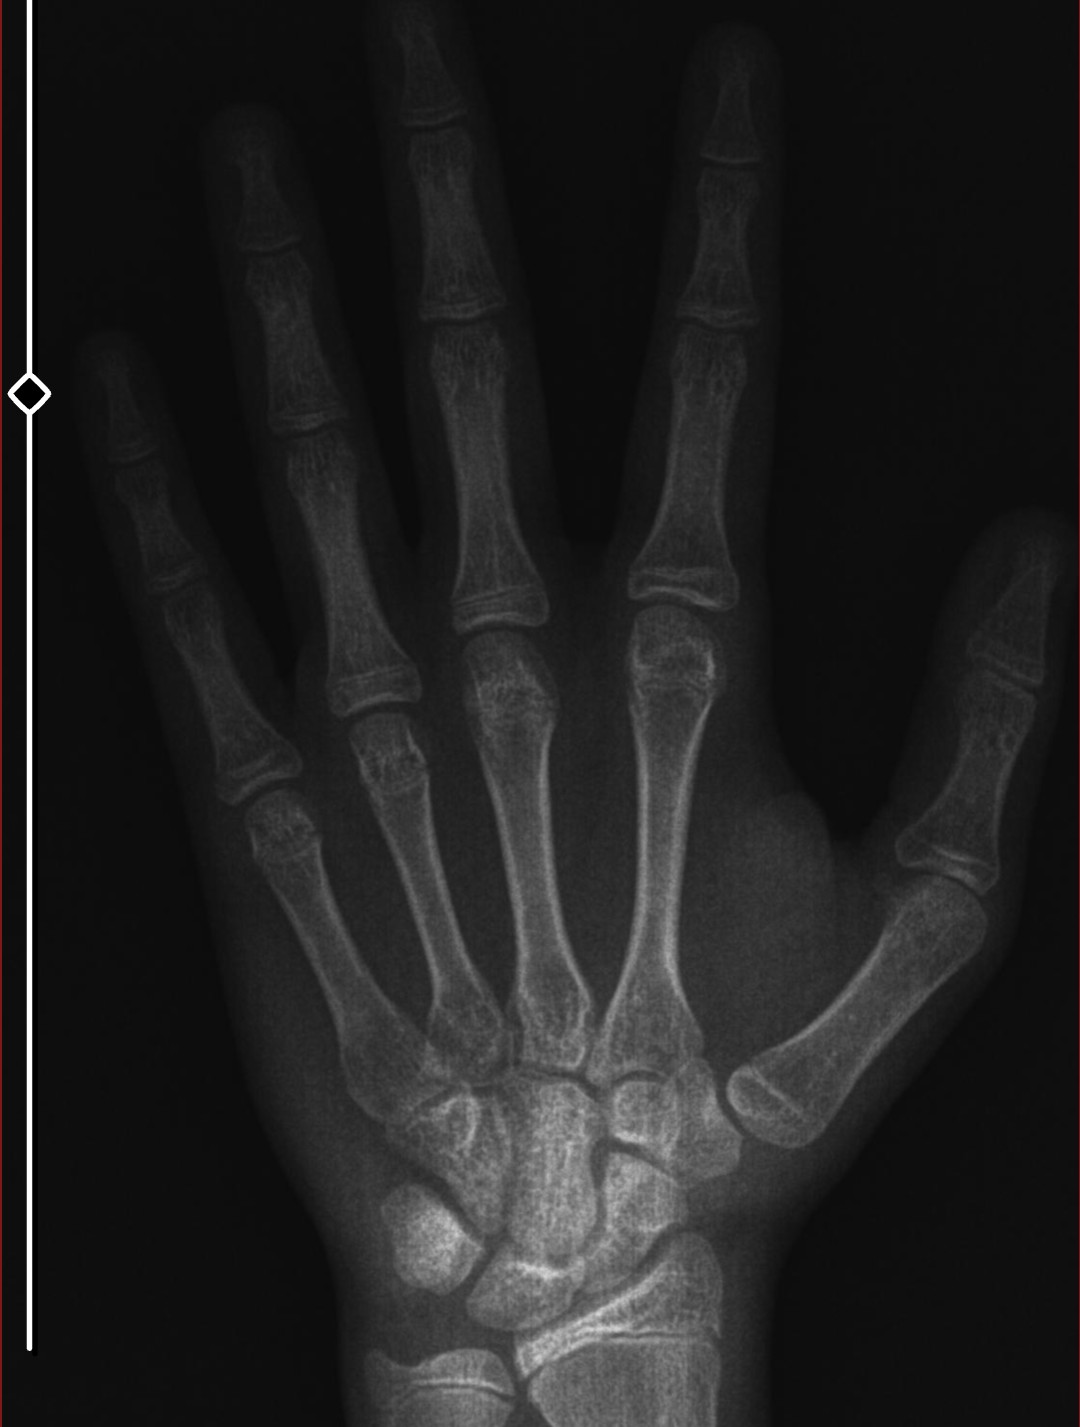

Bu xrayi 3 ay önce aldım 1.5-2 cm uzadım 177'yim şuan. Amcalarım 182 civarı baba tarafından kuzenlerim anneleri kıa olmalarına rağmen benden uzun. Annem 170 babam 180. Anne tarafım baya uzun dayılar kuzenler hepsi 190+. Kafayı yiyorum sülalenin en kısasıyım dışarıda annesi 155 babası 165 olup benden uzun olan insanları görünce dayanamıyorum. Fazlasında da göz yok 183'e ulaşsam yeter. Koltuk altı kıllarım 1 senedir çıkıyor sakal yok daha yeni yeni şakaklarda çene altında tüylenme hissediyorum ama uzamıyorlar ve gözükmüyorlar bile.

Knk epifiz plaklarina baktırman daha doğru olur çünkü once epifizler kapanır sonra parmaklar omurga falan bacağa baktir doktor söyler zaten ayrıca soyle diyeyim sana yasin küçük daha muhtemelen 180-185 arasına sabitlenirsin

Açık ama kapanmasına az kalmis

Bu xrayi 3 ay önce aldım 1.5-2 cm uzadım 177'yim şuan. Amcalarım 182 civarı baba tarafından kuzenlerim anneleri kıa olmalarına rağmen benden uzun. Annem 170 babam 180. Anne tarafım baya uzun dayılar kuzenler hepsi 190+. Kafayı yiyorum sülalenin en kısasıyım dışarıda annesi 155 babası 165 olup benden uzun olan insanları görünce dayanamıyorum. Fazlasında da göz yok 183'e ulaşsam yeter. Koltuk altı kıllarım 1 senedir çıkıyor sakal yok daha yeni yeni şakaklarda çene altında tüylenme hissediyorum ama uzamıyorlar ve gözükmüyorlar bile.View attachment 4238707

doktor copefuel vermekten baska bir sey yapmiyor kemik yasima 13 dedi o gun mutluluktan havaya uctum geld forumlara dclere attim herkes max 3-4 cm diyor babamdan kisa olacam annem de kisa degil 170 diger akrabalardan bahsetmiyorum bile ortalamalaei 187-190

doktora sormaya utandimda kapalimi bi baksaniz